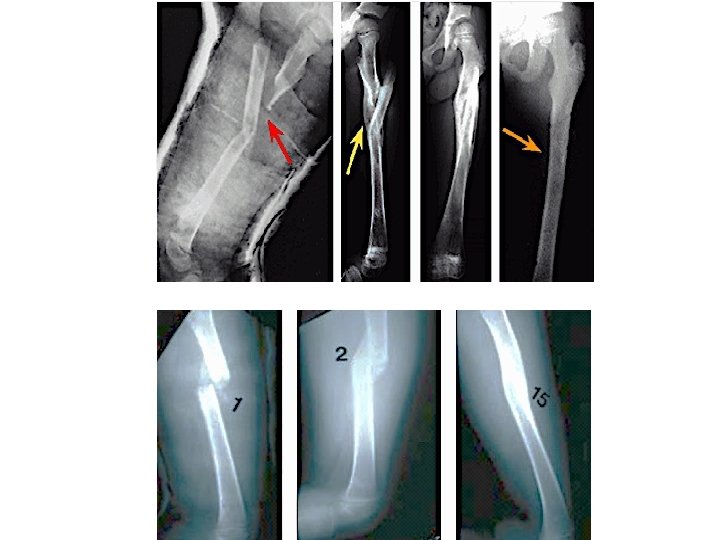

Femoral Shaft Fractures

Femoral Shaft # • 1. 6% of all pediatric # • M>F • Age: – (2 – 4) years old – Mid-adolescence • Adolescence >90% due to RTA

Femoral Shaft #- Mechanism of Injury • Direct trauma: – RTA, – Fall, or • Indirect trauma: – Rotational injury • Pathologic #: – Osteogenesis imperfecta – Nonossifying fibroma – Bone cysts – Tumors

Femoral Shaft #- Treatment 6 – 12 y: • Flexible I. M. N • Bridge Plating • External Fixation

Femoral Shaft #- Treatment 6 – 12 y: • Flexible IMN • Bridge Plating • External Fixation

Femoral Shaft #- Treatment 6 – 12 y: • Flexible IMN • Bridge Plating • External Fixation: – Multiple injuries – Open fracture – Comminuted # – Unstable patient

Femoral Shaft #- Treatment 12 y to skeletal maturity: • Intramedullary fixation with either: – Flexible nails, or – Locked I. M nail